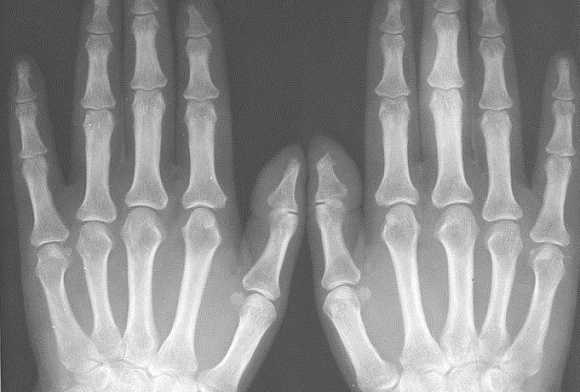

СНИМКИ КИСТИ В ПРЯМОЙ ЛАДОННОЙ ПРОЕКЦИИ

Назначение снимка — изучение скелета кисти в целом, включая запястье, пястье и фаланги.

Укладка больного для выполнения снимка. Больной сидит боком к краю стола. Рука отведена, согнута в локтевом суставе; кисть находится в положении пронации. Пальцы выпрямлены и сомкнуты.

Кассета размером 18Х 24 см расположена в плоскости стола. Ладонь плотно прилежит к кассете.

Средней поперечной линии кассеты соответствует проекция головок пястных костей.

Пучок рентгеновского излучения направлен отвесно на головку III пястной кости (рис. 367).

Информативность снимка. На снимке выявляются дистальные метаэпифизы костей предплечья, рентгеновская суставная щель лучезапястного сустава, запястье, пястные кости и фаланги. Хорошо видны рентгеновские суставные щели мелких суставов кисти.

При правильно подобранных физико-технических параметрах съемки четко видна губчатая структура костей запястья, концов пястных костей и фаланг. В телах коротких трубчатых костей определяются мозговые полости и корковое вещество (рис. 368).